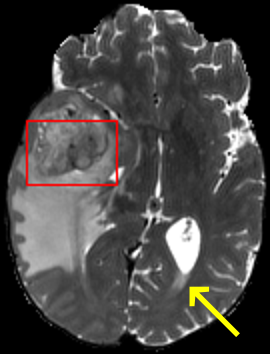

In the MRI CT translation in the Gold Atlas dataset (Fig. 8), major bones and muscles are translated faithfully. Yet, diffusion sampling leads to some inaccuracies in the outline of bones and hallucinations of the textures of inner organs. Conversely, regression sampling faithfully translates bones while still blurring the inner organs and generating artifacts. This indicates that rendering CTs is under-defined by the given MRI guidance alone.

Diffusion sampling YODA results in hallucinated organ shapes and textures that smoothen out and disappear when increasing the in Exp sampling or when using regression sampling. Regression sampling creates some artifacts. Note that, for all methods, the translation quality for inner organs is rather poor, whereas bone and muscle translation is reliable.

When benchmarking on the more heterogeneous and lower-quality BraTS dataset (Tab. 2, left), regression sampling of YODA achieved significantly better images than all competing methods in terms of PSNR, SSIM, and downstream glioma segmentation. Similar results were obtained in the IXI dataset (Tab. 2, right), where YODA significantly outperformed all competing methods in SSIM and PSNR. In the full-brain segmentation conducted from the synthetic images, YODA’s images were significantly better than all competing methods in at least either the Dice score or the HD. In the MRI CT task on the small pelvic dataset, regression and ExpA sampling achieved the highest SSIM, whereas the DB of Choo et al. [31] had the highest PSNR. Both, regression and ExpA sampling YODA also performed competitively in the downstream segmentation task. Note that, for all methods, the translation of inner organs was rather poor and included either texture hallucination (ResViT, I2I-Mamba, diffusion-sampling YODA) or an over-smooth image appearance (Choo et al. [31], SelfRDB, SynDiff, ExpA and regression sampling YODA, Fig. 8).